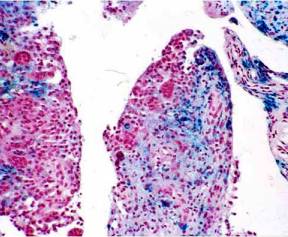

El tejido obtenido de las zonas solidas de la lesión tumoral compleja de la pantorrilla, al examen anatomopatológico informa: material constituido por abundantes macrófagos con pigmentos en su interior, linfocitos maduros y abundantes células gigantes. Compatible con Sinovitis Vellonodular Pigmentada. Imagen 10

Imagen 10. Proliferación de células sinoviales y células gigantes multinucleadas